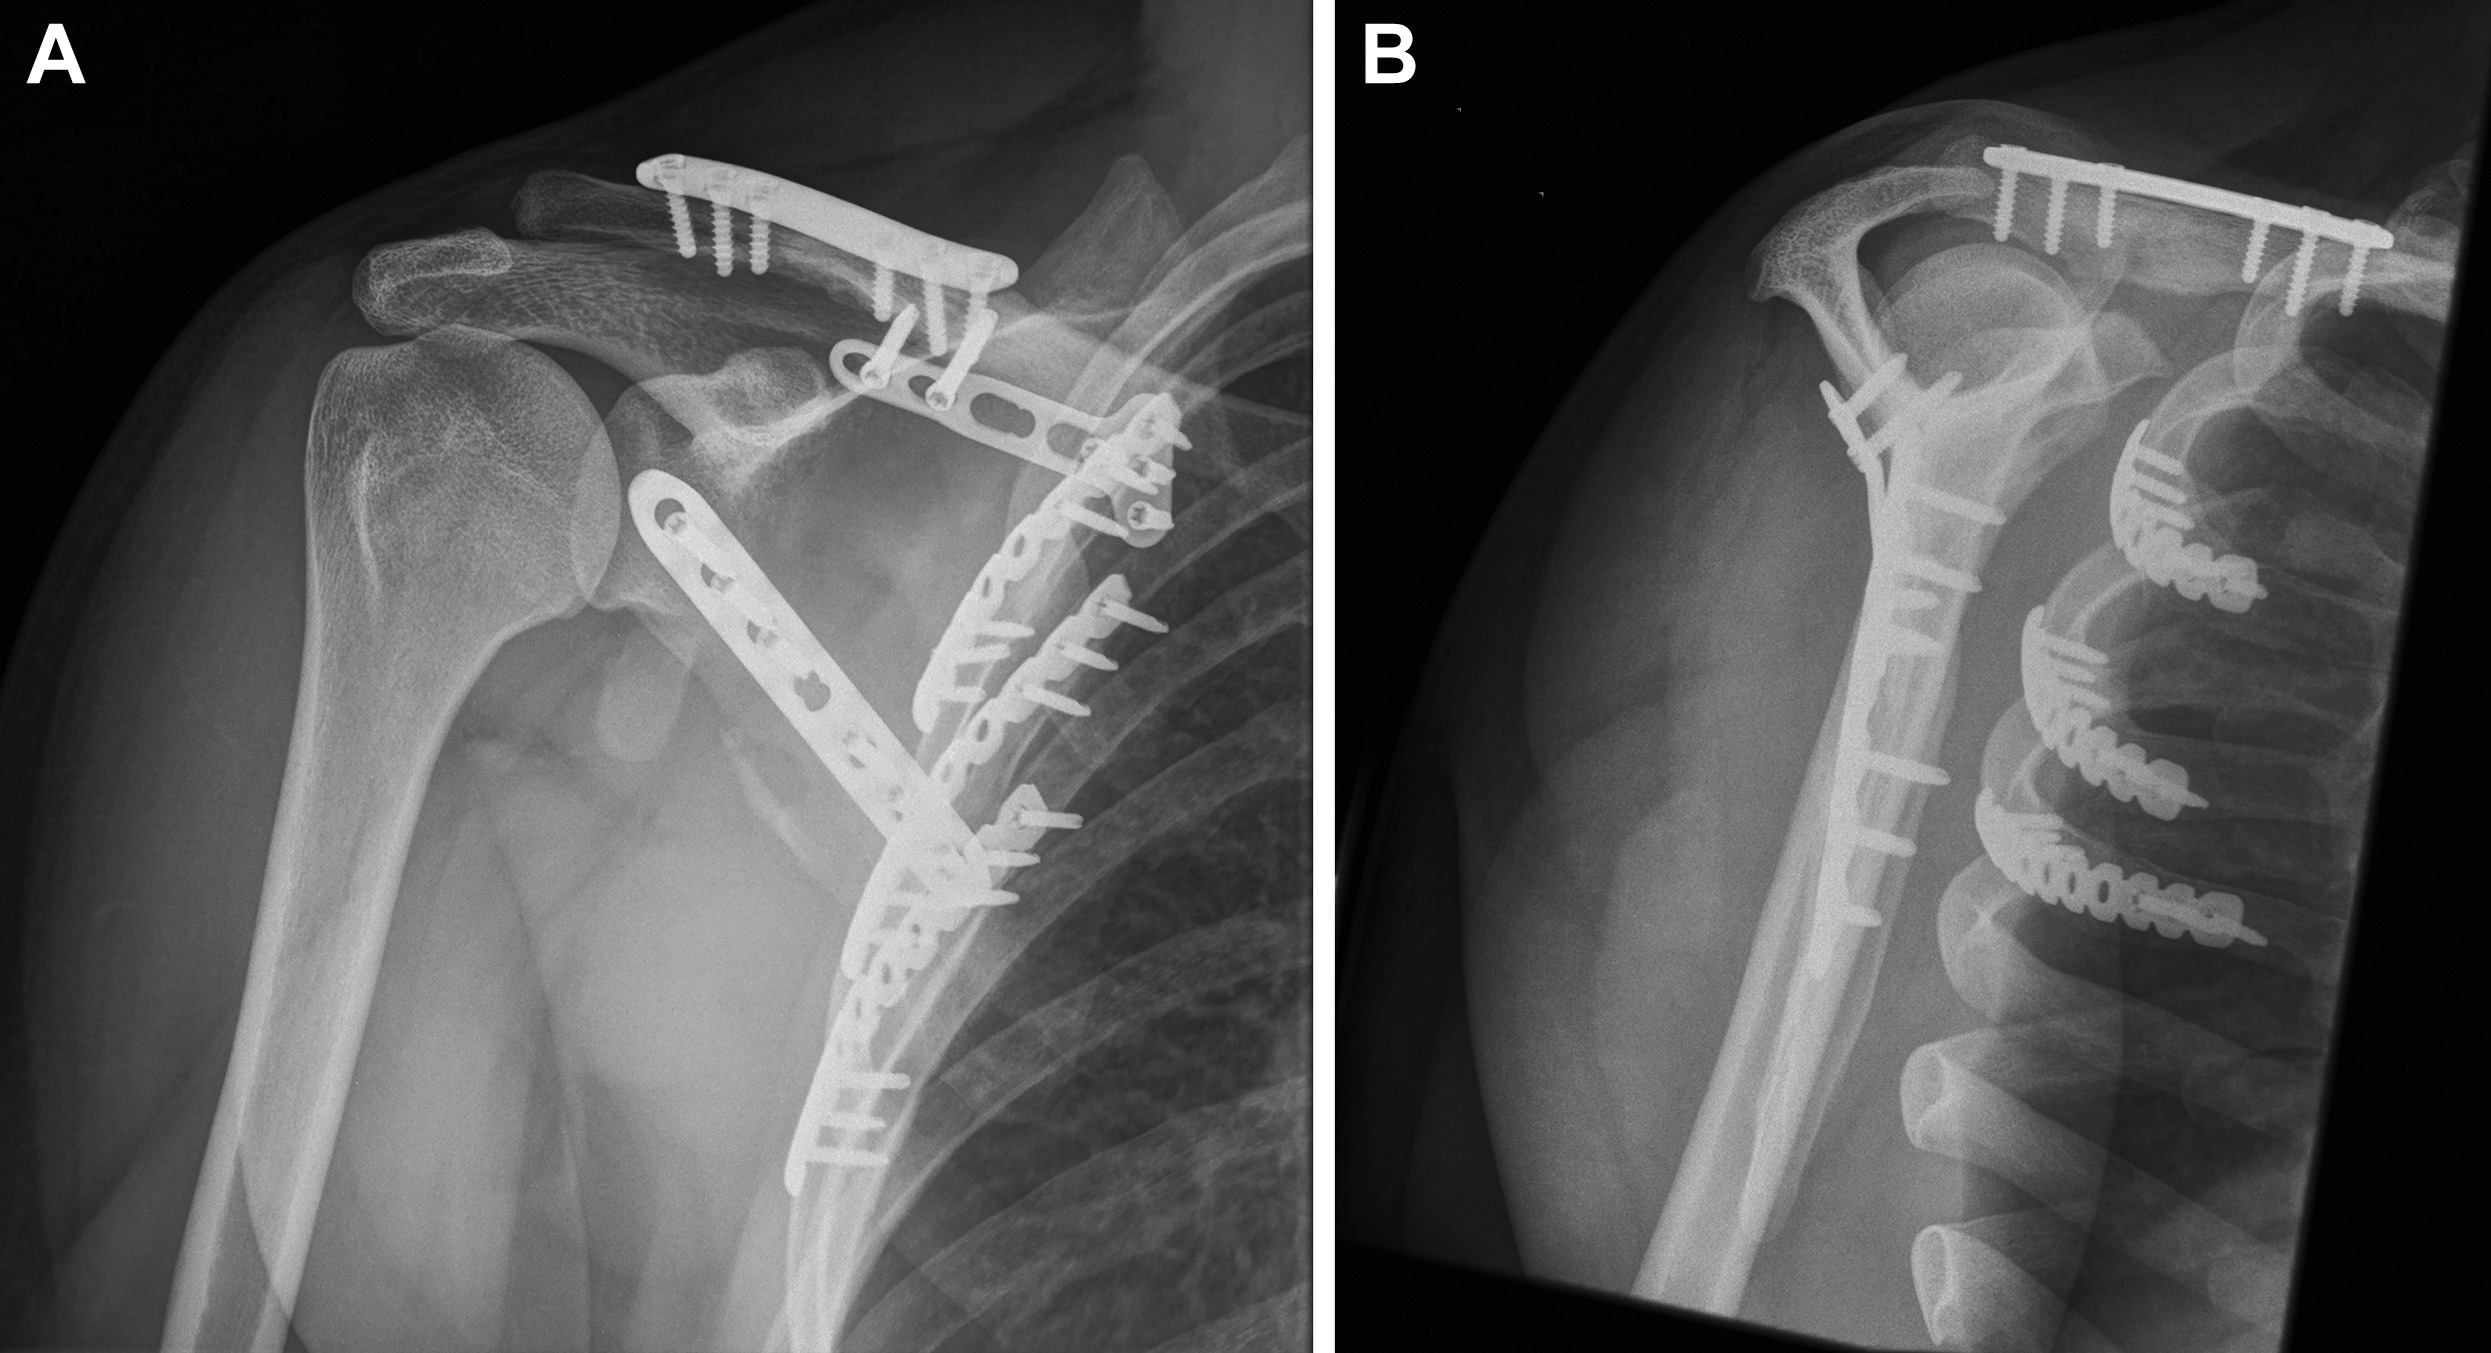

- 수술 치료

- 금속 핀, 플레이트, 나사 고정

- 골절이 심하거나 어긋난 경우

- 기능 회복을 위해 정렬이 중요한 경우

특히 핀 고정 수술은 골절 부위를 정확히 맞추고 빠르게 안정화할 수 있다는 장점이 있습니다. 다만 수술 이후에도 재활이 반드시 병행되어야 정상적인 기능 회복이 가능합니다.